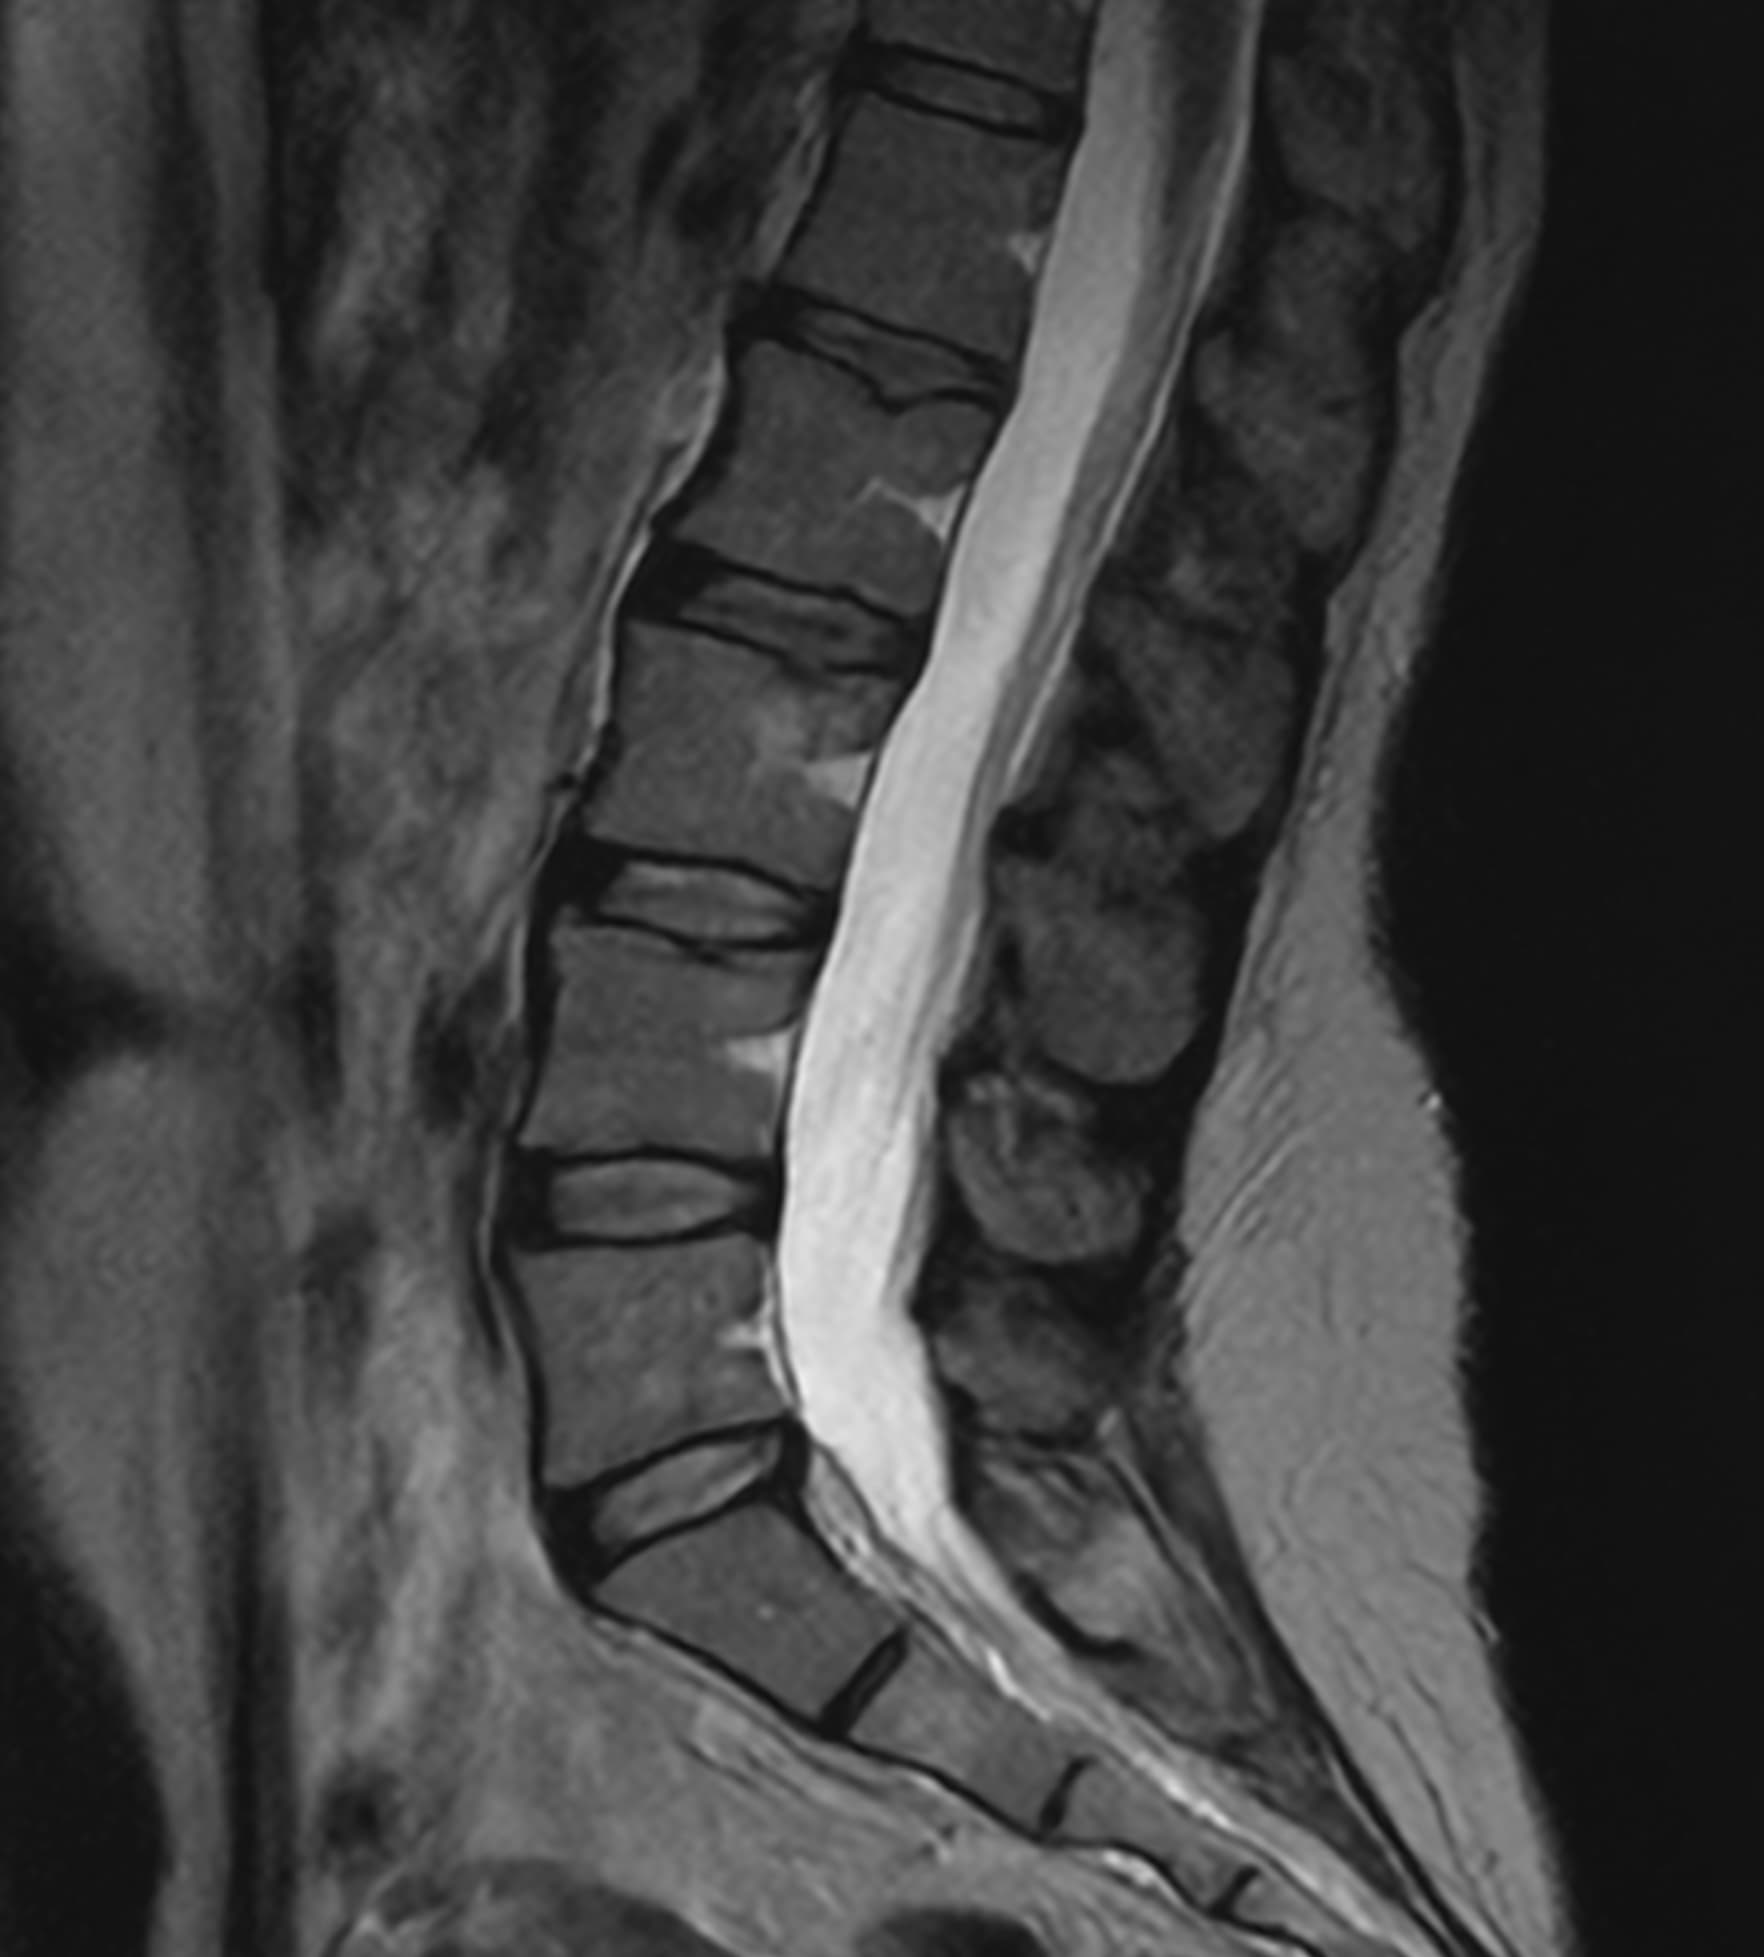

See real-world examples of SwiftMR™ across various MRI systems and anatomical regions